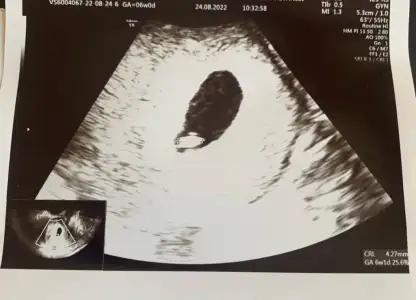

kızlar benım ultrasona bakar mısınız . aşağıda sayılar falan yazıyor ndır onlar yardımcı olur musunuz

Eklentiler

• WhatsApp Image 2022-08-29 at 11.02.11.webp

WhatsApp Image 2022-08-29 at 11.02.11.webp

26,9 KB · Görüntüleme: 78